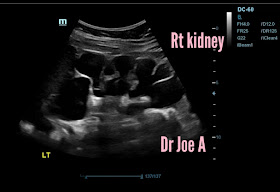

Moderate right hydronephrosis also.